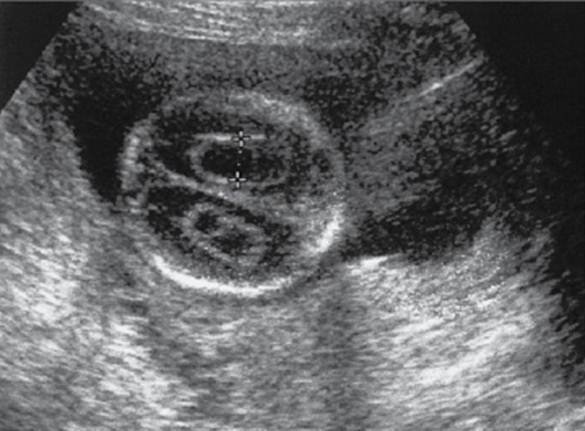

Choroid plexus cysts